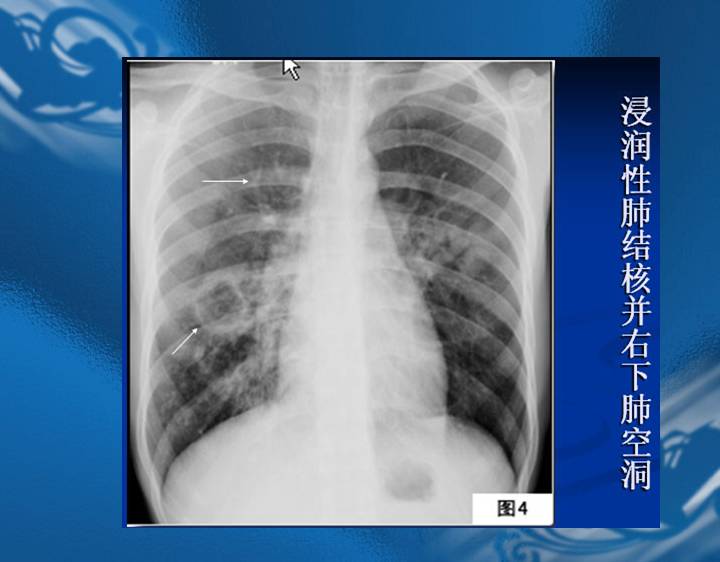

执业医师资格考试“实践技能”影像学辅导资料